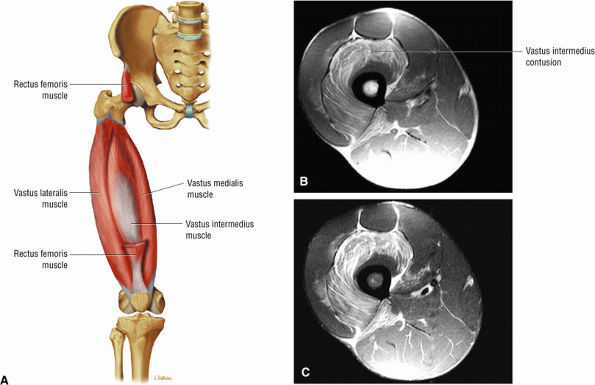

The anterior muscles of the thigh, including the sartorius (Fig. 3.5), the rectus femoris (Fig. 3.6), the vastus lateralis (Fig. 3.7), the vastus medialis (Fig. 3.8), and the vastus intermedius (Fig. 3.9). The vastus lateralis, vastus medialis, vastus intermedius, and rectus femoris are the quadriceps muscles.

![]() |

FIGURE 3.7 ● VASTUS LATERALIS The vastus lateralis extends the leg and flexes the thigh (hip) and is one of the quadriceps muscles (vastus lateralis, vastus medialis, vastus intermedius, and rectus femoris). Quadriceps muscle fibers are predominantly type II and are adapted for rapid forceful activity. The vastus lateralis obliquus (VLO) fibers of the vastus lateralis muscle interdigitate with the lateral intermuscular septum and insert onto the patella. In a lateral retinacular release, the VLO may be selectively sectioned without involving the main vastus lateralis tendon proper.

FIGURE 3.8 ● VASTUS MEDIALIS The vastus medialis extends the leg and pulls the patella medially. The quadriceps muscle group includes the vastus lateralis, the vastus medialis, the vastus intermedius, and the rectus femoris. The quadriceps muscles converge distally, forming the quadriceps tendon, which inserts on the proximal pole of the patella. The vastus medialis assists in preventing patellar dislocations and may be weak in patellofemoral disorders. Therefore, vastus medialis obliquus injuries are frequently associated with transient patellar dislocation.

FIGURE 3.9 ● VASTUS INTERMEDIUS The vastus intermedius extends the leg and covers the articularis genu. Quadriceps (vastus lateralis, vastus medialis, vastus intermedius, and rectus femoris) injuries, including strains and tendon ruptures, result from eccentric muscle contractions. The articularis genu muscle represents a few separate muscle fibers deep to the vastus intermedius and is responsible for contracting the knee joint capsule superiorly in extension.